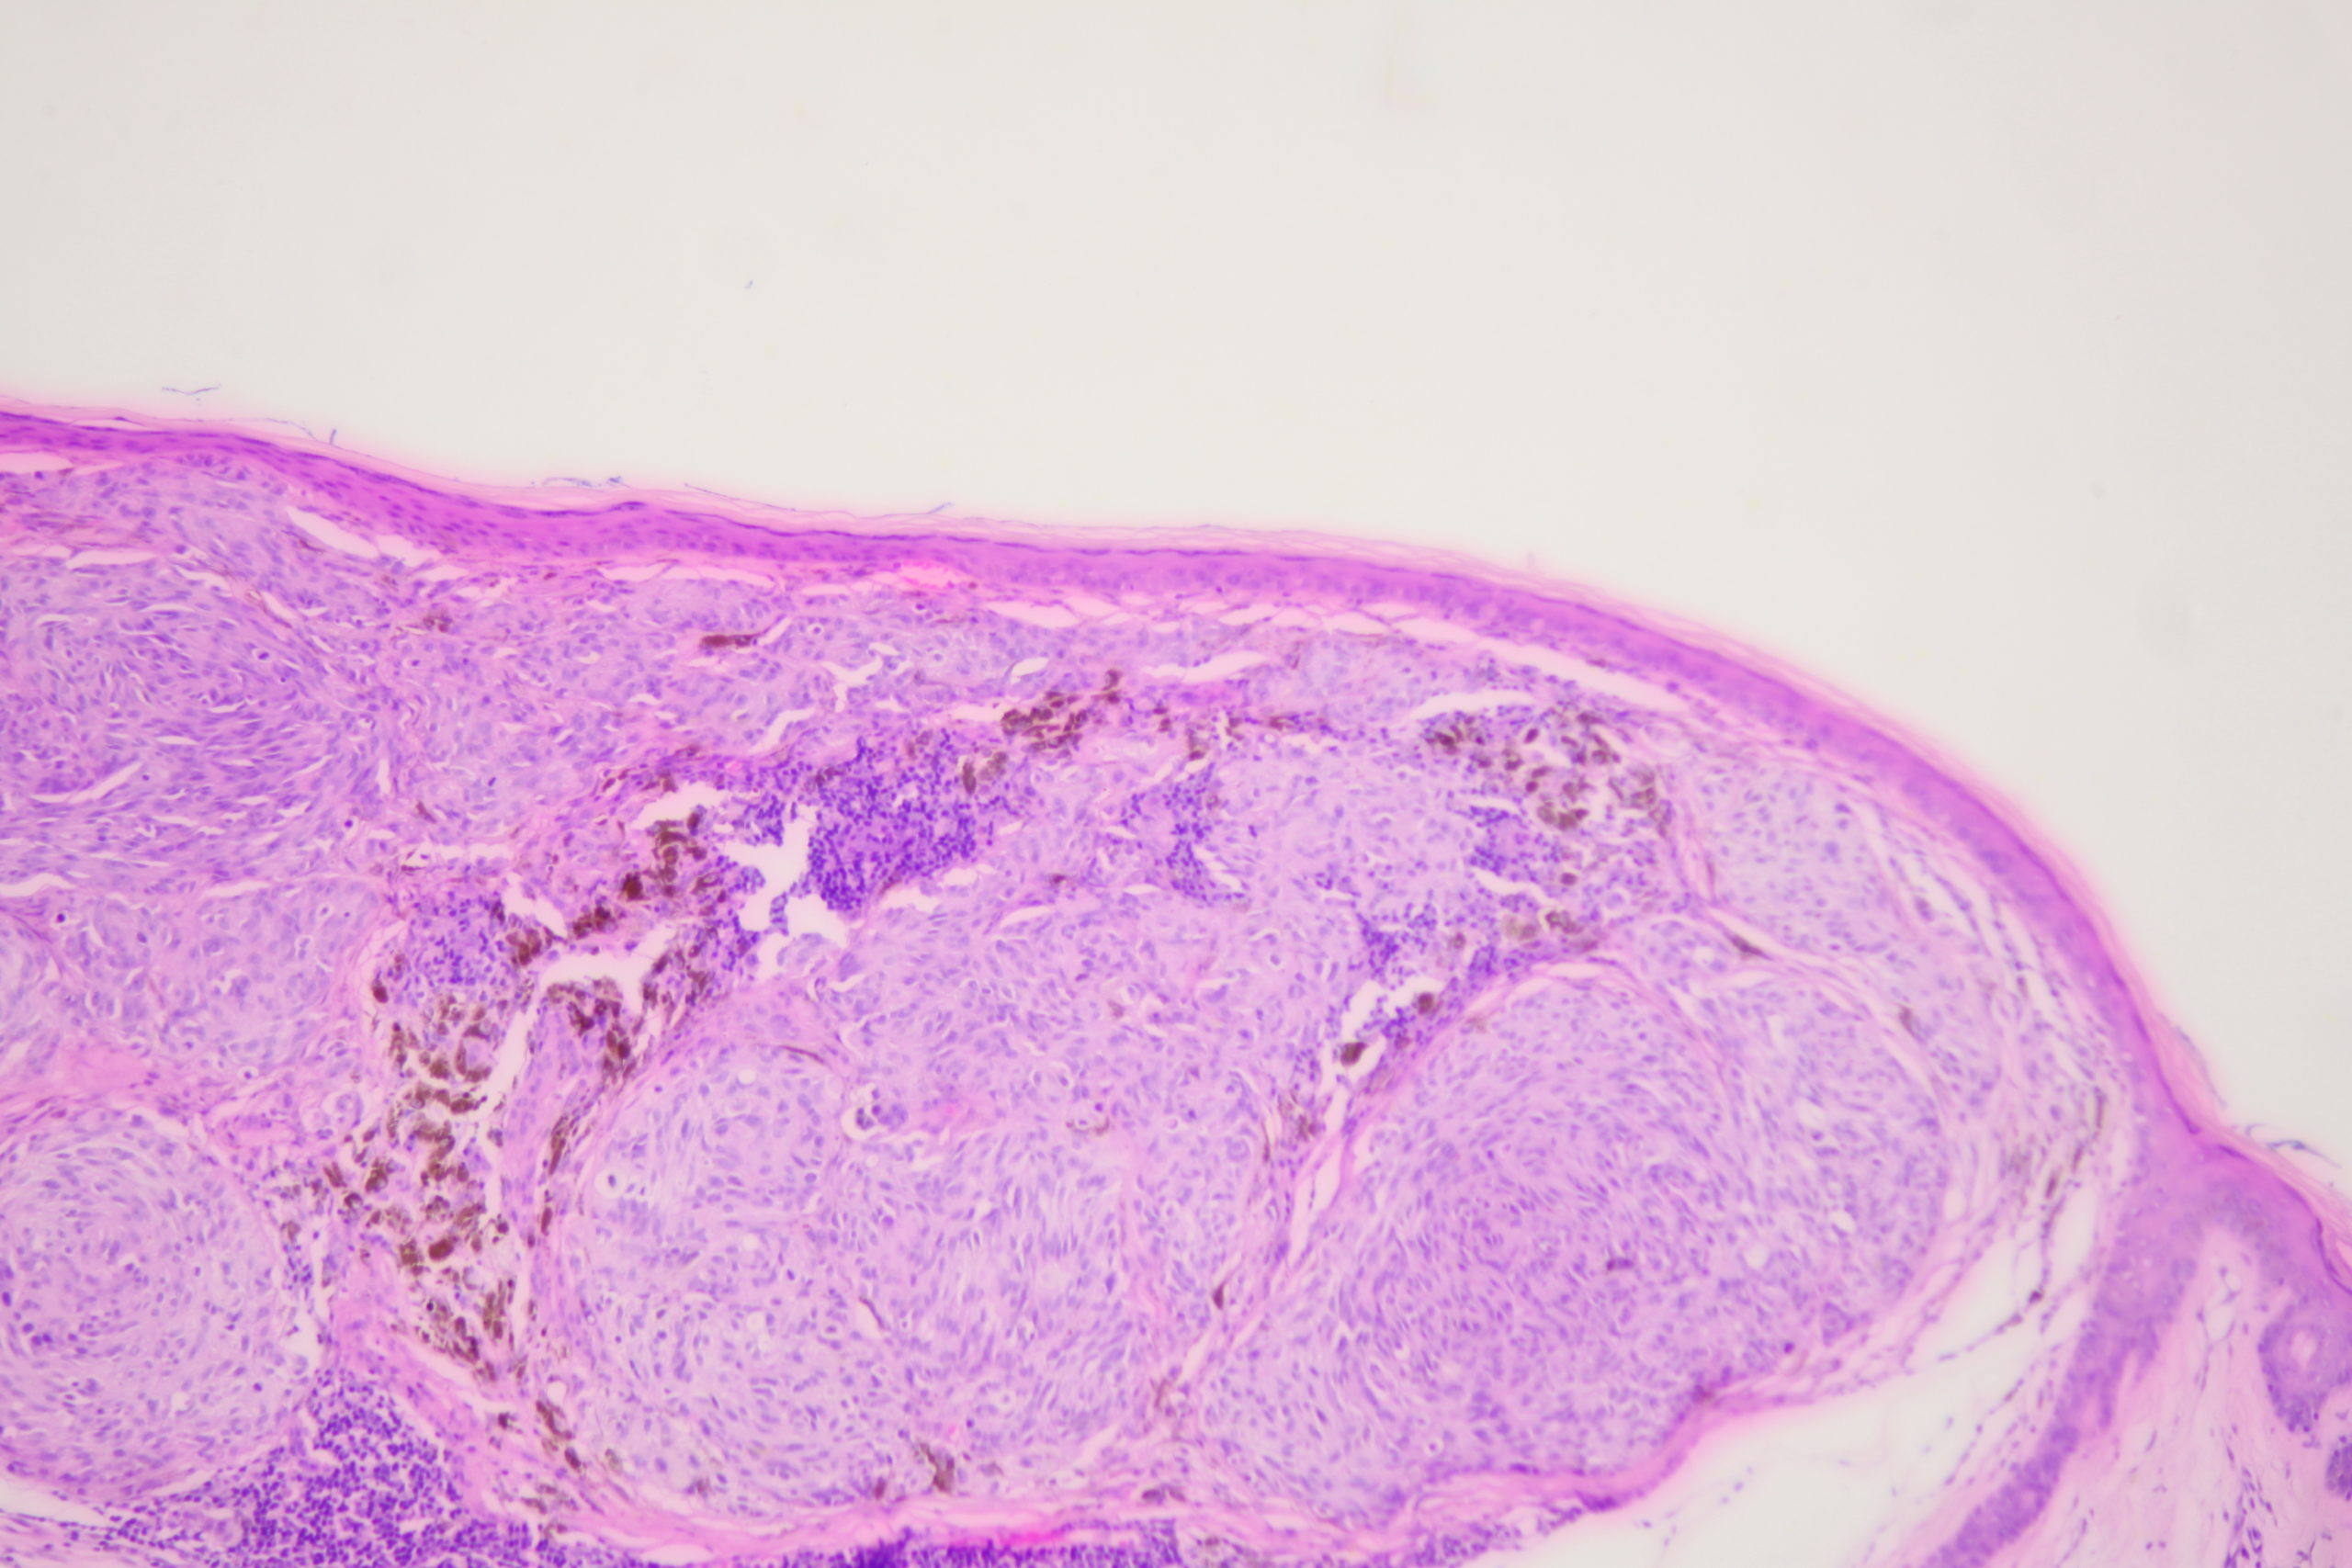

Site: Back

Diagnosis: Melanoma nodular

Pigmented lesion upper back

This lesion was noted during a routine skin examination in an elderly patient on immunosuppressives for an autoimmune disease.

The lesion was a 0.55 mm thick Clark level 3 nodular melanoma.